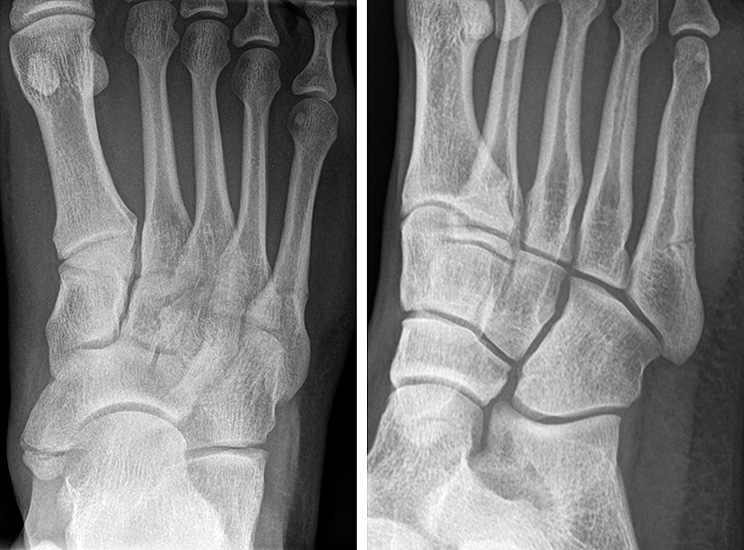

Illustration der Lawrence und Botte Klassifikation:<br>

Zone I: Avulsionsfraktur der Tuberositas <br>

Zone II: Jones’ Fraktur <br>

Zone III: Diaphysäre Stressfraktur<br>

Abbildung 1

Die in der Literatur am häufigsten verwendete Klassifikation ist die 1993 publizierte, anatomische Klassifikation von Lawrence und Botte 6. Diese basiert auf einer retrospektiven Fallserie und unterscheidet drei Frakturzonen (Abb. 1).

Zone II befindet sich auf Höhe der Articulatio zwischen MT IV und V. Die Zone I liegt proximal, die Zone III distal davon. Interessanterweise vermischen Lawrence und Botte Unfallmechanismen (Avulsionsfraktur/Stressfraktur) und deskriptive Terminologie (Jones’ Fraktur) in ihrer Klassifikation. Eine Vereinfachung dieser Klassifikation publizierten Polzer et al. 2012 7. Basierend auf den Ergebnissen von sechs prospektiven Behandlungsstudien (systematische Literaturrecherche), schlussfolgerten die Autoren, dass Lawrence und Botte Zone I und II Frakturen zusammengefasst werden könnten (Metaphysäre Frakturen). Zone III Frakturen werden als Meta-Diaphysär beschrieben.